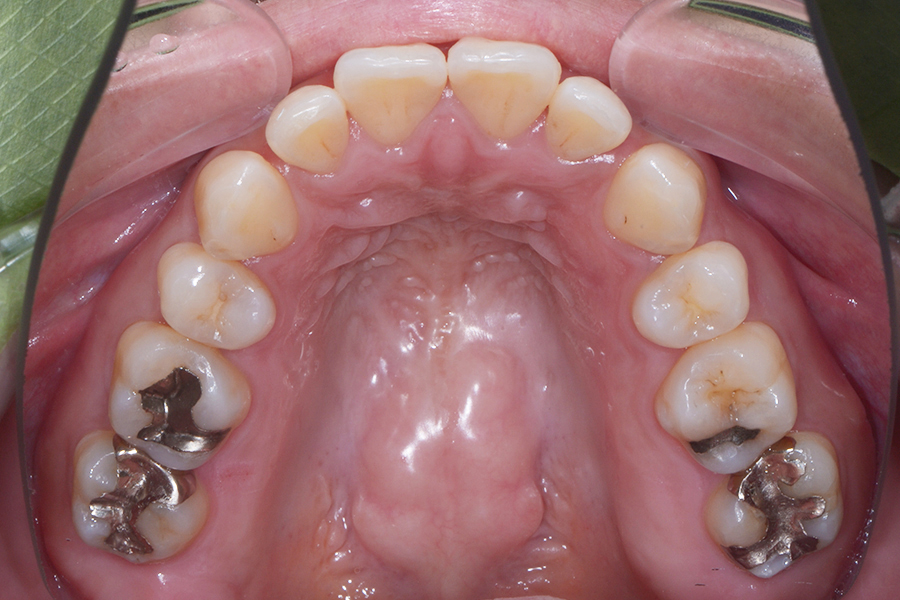

【30代男性】

前歯と奥歯の

ねじれを治したい

【矯正歯科治療】

- 担当医

- 三留先生

- 主訴

- 前歯と奥歯のねじれを治したい

- 期間

- 治療期間10か月

- 費用

- 治療費20万(別途調整料)

※デンタルローン60回 ¥3,800/月

- 治療内容

- 上顎ラビアル矯正(表側矯正)

- 治療に伴うリスク

- 後戻り